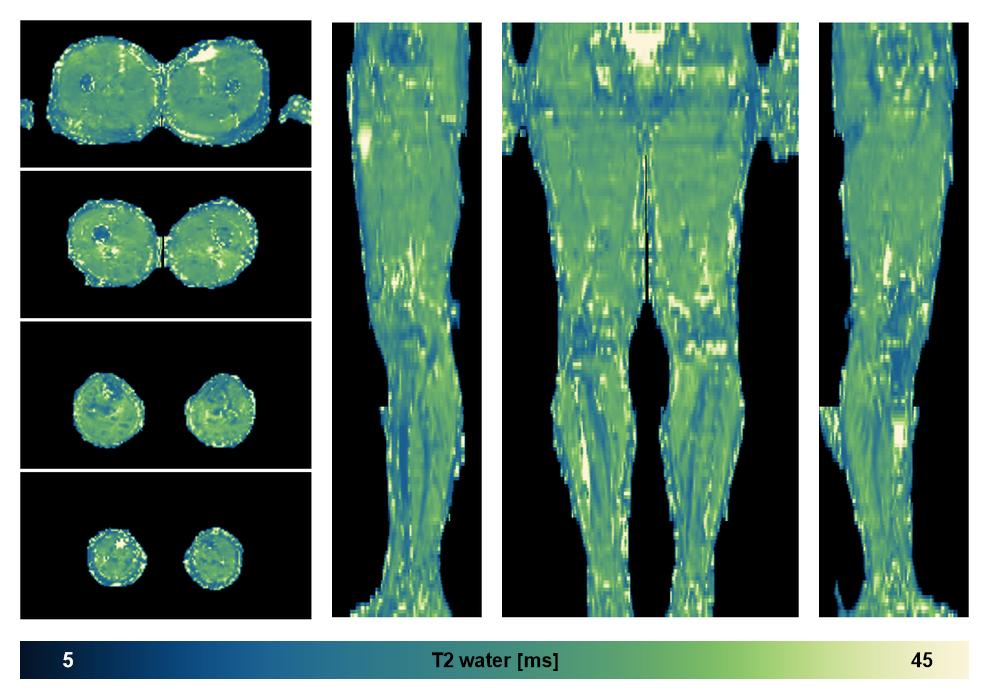

• Water only T2 relaxation time

The water only T2 relaxation time of the lower extremity obtained from multi echo spin echo t2 mapping with EPG based reconstruction.